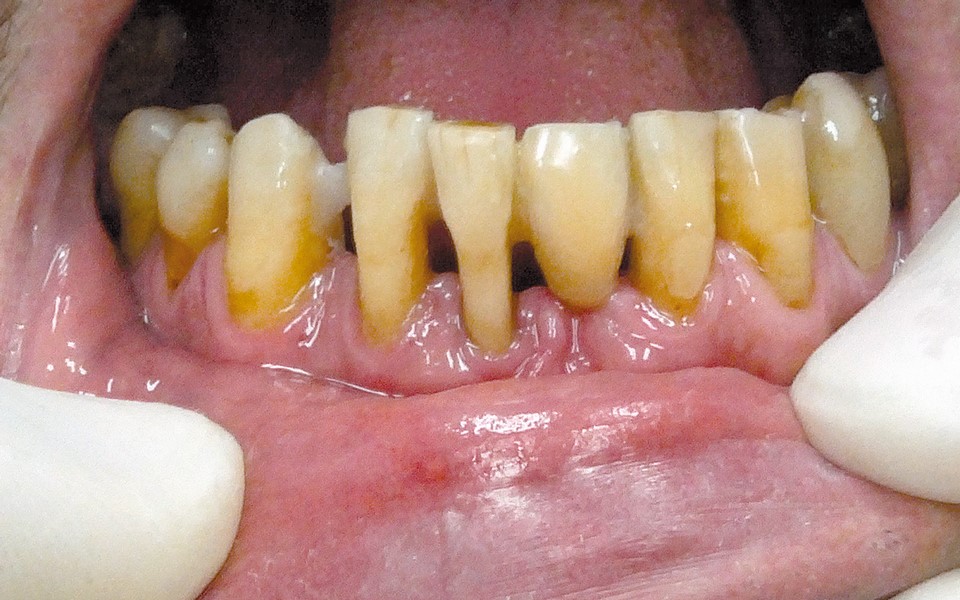

One of the more popular methods of stabilising loose teeth is to splint them. This method, aiding other methods of treatment, is generally used. One of the most modern materials used in dentistry for splinting teeth, is polyamide tape. In the case described the authors show how to simplify the whole procedure and limit the risk of making a mistake, particularly in the situation of total loss of one tooth. This was achieved thanks to the use of an index made out of transparent silicone.

Jedną z popularniejszych metod stabilizacji zębów rozchwianych jest ich szynowanie. Metoda ta, wspierająca inne metody leczenia, jest powszechnie stosowana. Jednym z najnowocześniejszych materiałów wykorzystywanych w stomatologii do szynowania zębów jest taśma poliaramidowa. W opisanym przypadku autorzy pracy przedstawiają sposób uproszczenia całej procedury i ograniczenia ryzyka popełnienia błędu, szczególnie w sytuacji całkowitej utraty zęba. Uzyskano to dzięki zastosowaniu indeksu wykonanego z przezroczystego silikonu.